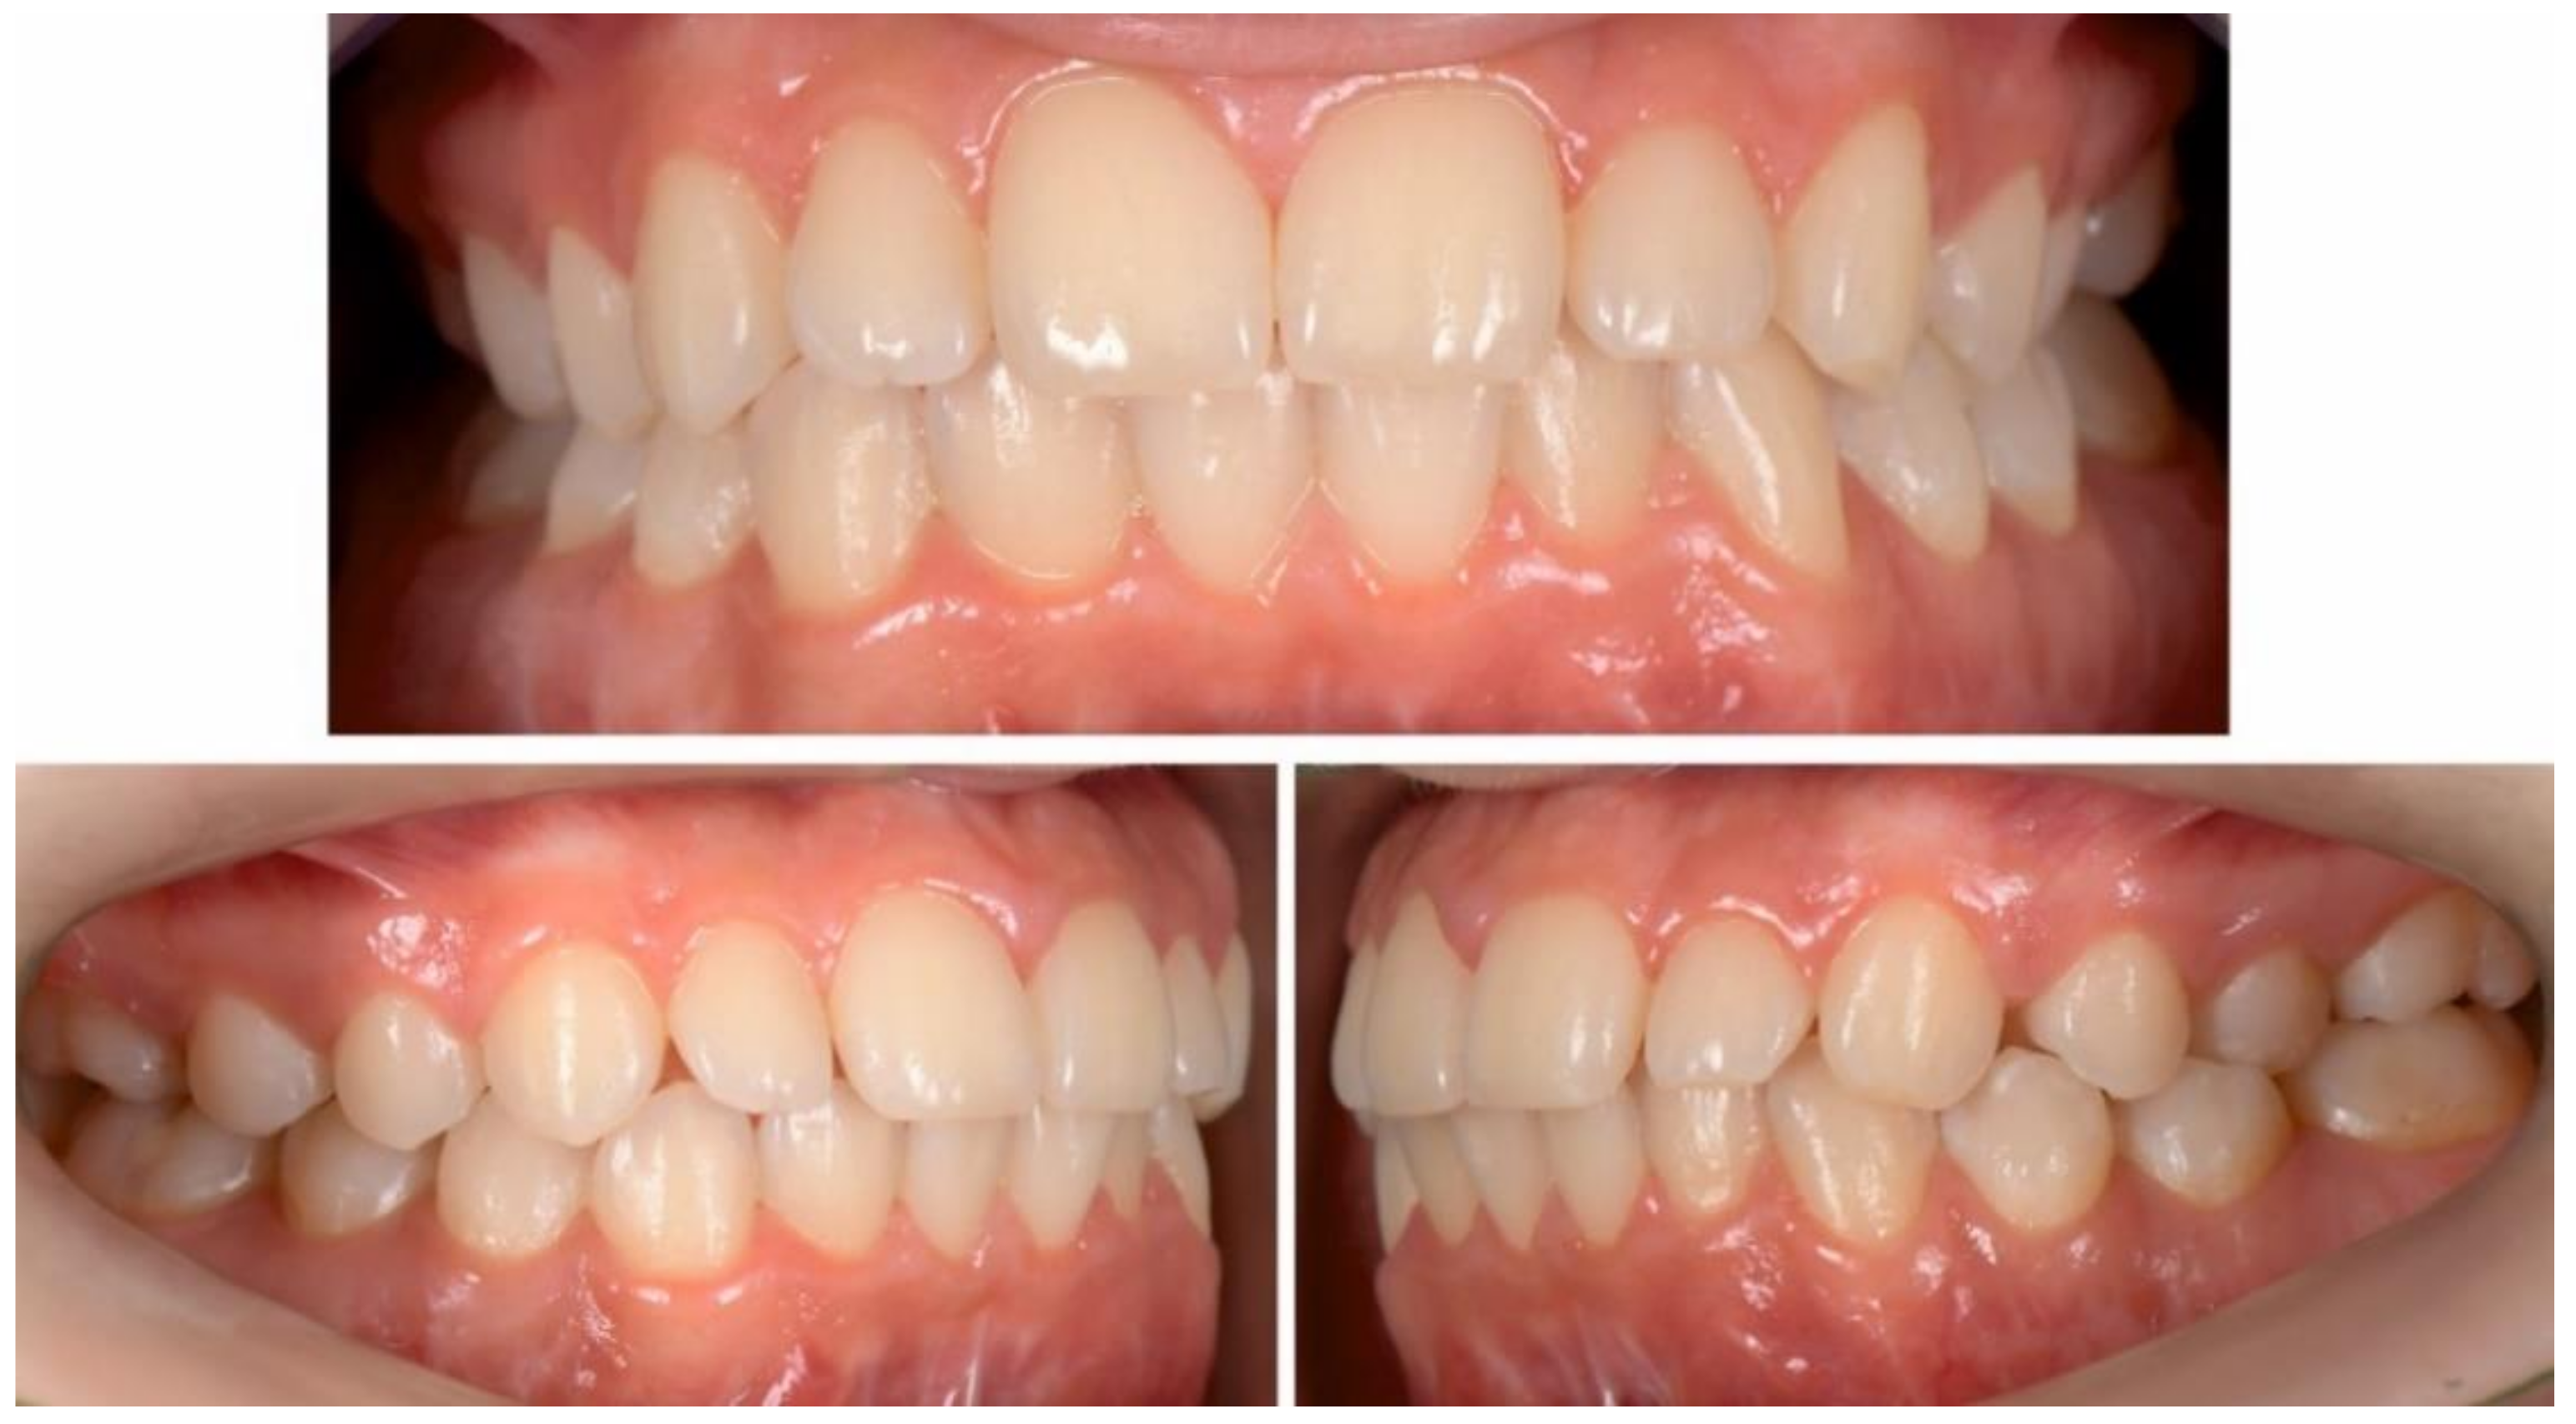

3. Results